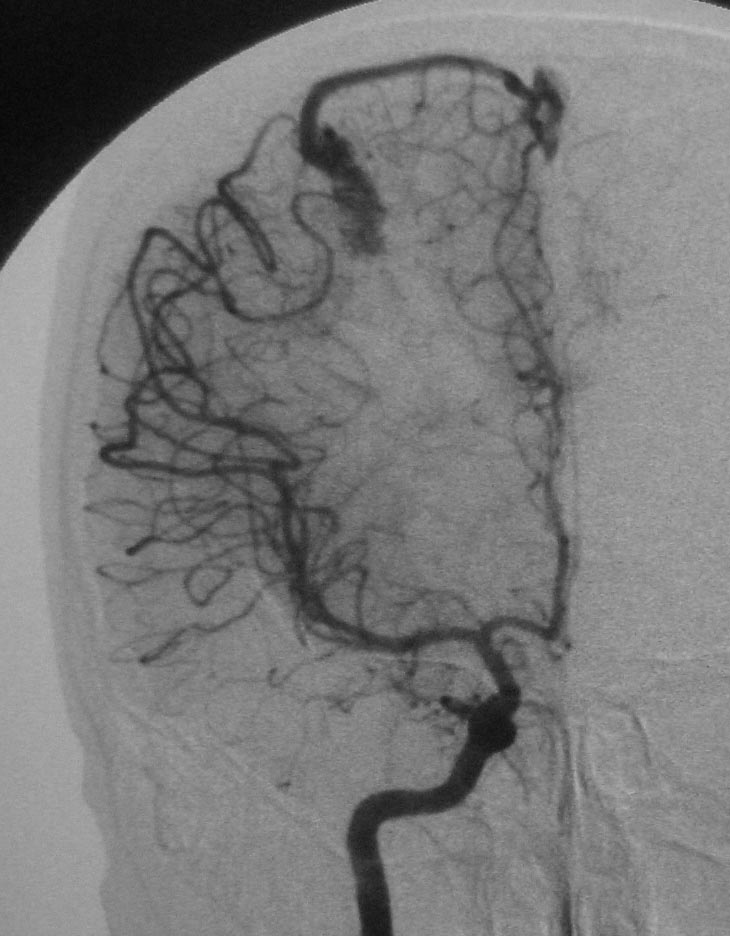

标题: DSA0118:脑血管造影

典型的avm

有供血动脉、畸形血管团、引流静脉,支持典型avm。

大脑中动脉的皮质支通过引流静脉汇入上失状窦

大脑中前动脉向一条静脉供血,是哪个类型的avm?/